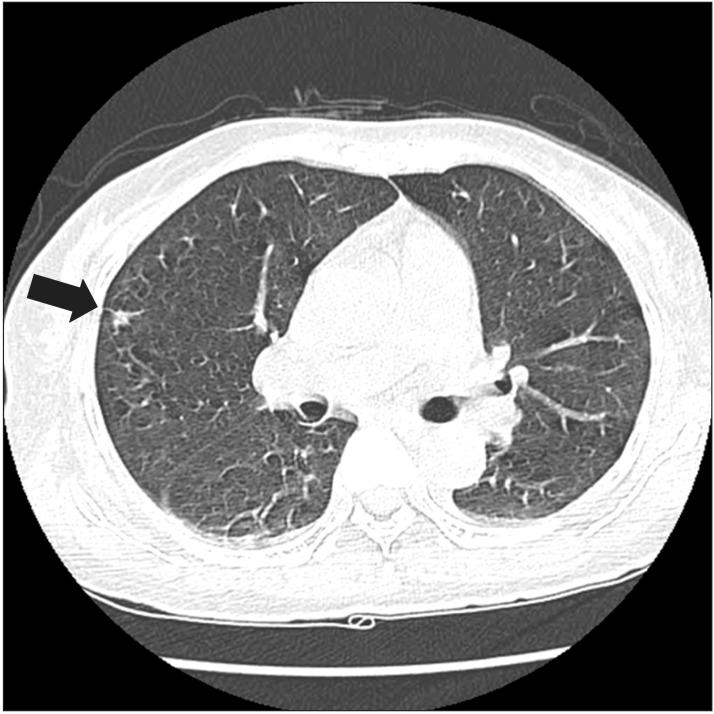

Churg-Strauss syndrome (CSS) is a rare systemic necrotizing vasculitis. Cranial nerve involvement is very rare in CSS. A 59-year-old woman had complained of both hearing impairments for eight months and left facial palsy for three months. Left facial and cochlear neuropathies were detected in electrodiagnostic studies. Paranasal sinus computed tomography (CT) showed chronic pansinusitis. Chest CT revealed eosinophilic infiltration in the right upper lobe. Tissue biopsy of the right inferior turbinate displayed necrotizing vasculitis with eosinophilic infiltration. She was diagnosed as CSS, based on the presence of eosinophilia, pulmonary infiltration, paranasal sinusitis, and biopsy containing blood vessels with extravascular eosinophils. She was treated with intravenous and oral steroids and azathioprine, showing relatively good prognosis on facial palsy and hearing impairment. We report a very rare case of CSS presented with hearing impairment and facial palsy.